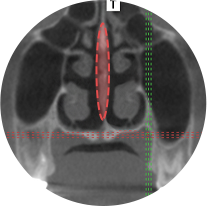

Also, nasal space and septal shape is examined through 3D-CT and thorough diagnosis to aim for functionally comfortable result.

TS provides an accurate solution by considering both aesthetical and functional aspects with precise analysis from the most ideal shape to the invisible function inside the nose based on individual needs.

Ideal Ratio

Considering not only the shape but also the overall facial proportion